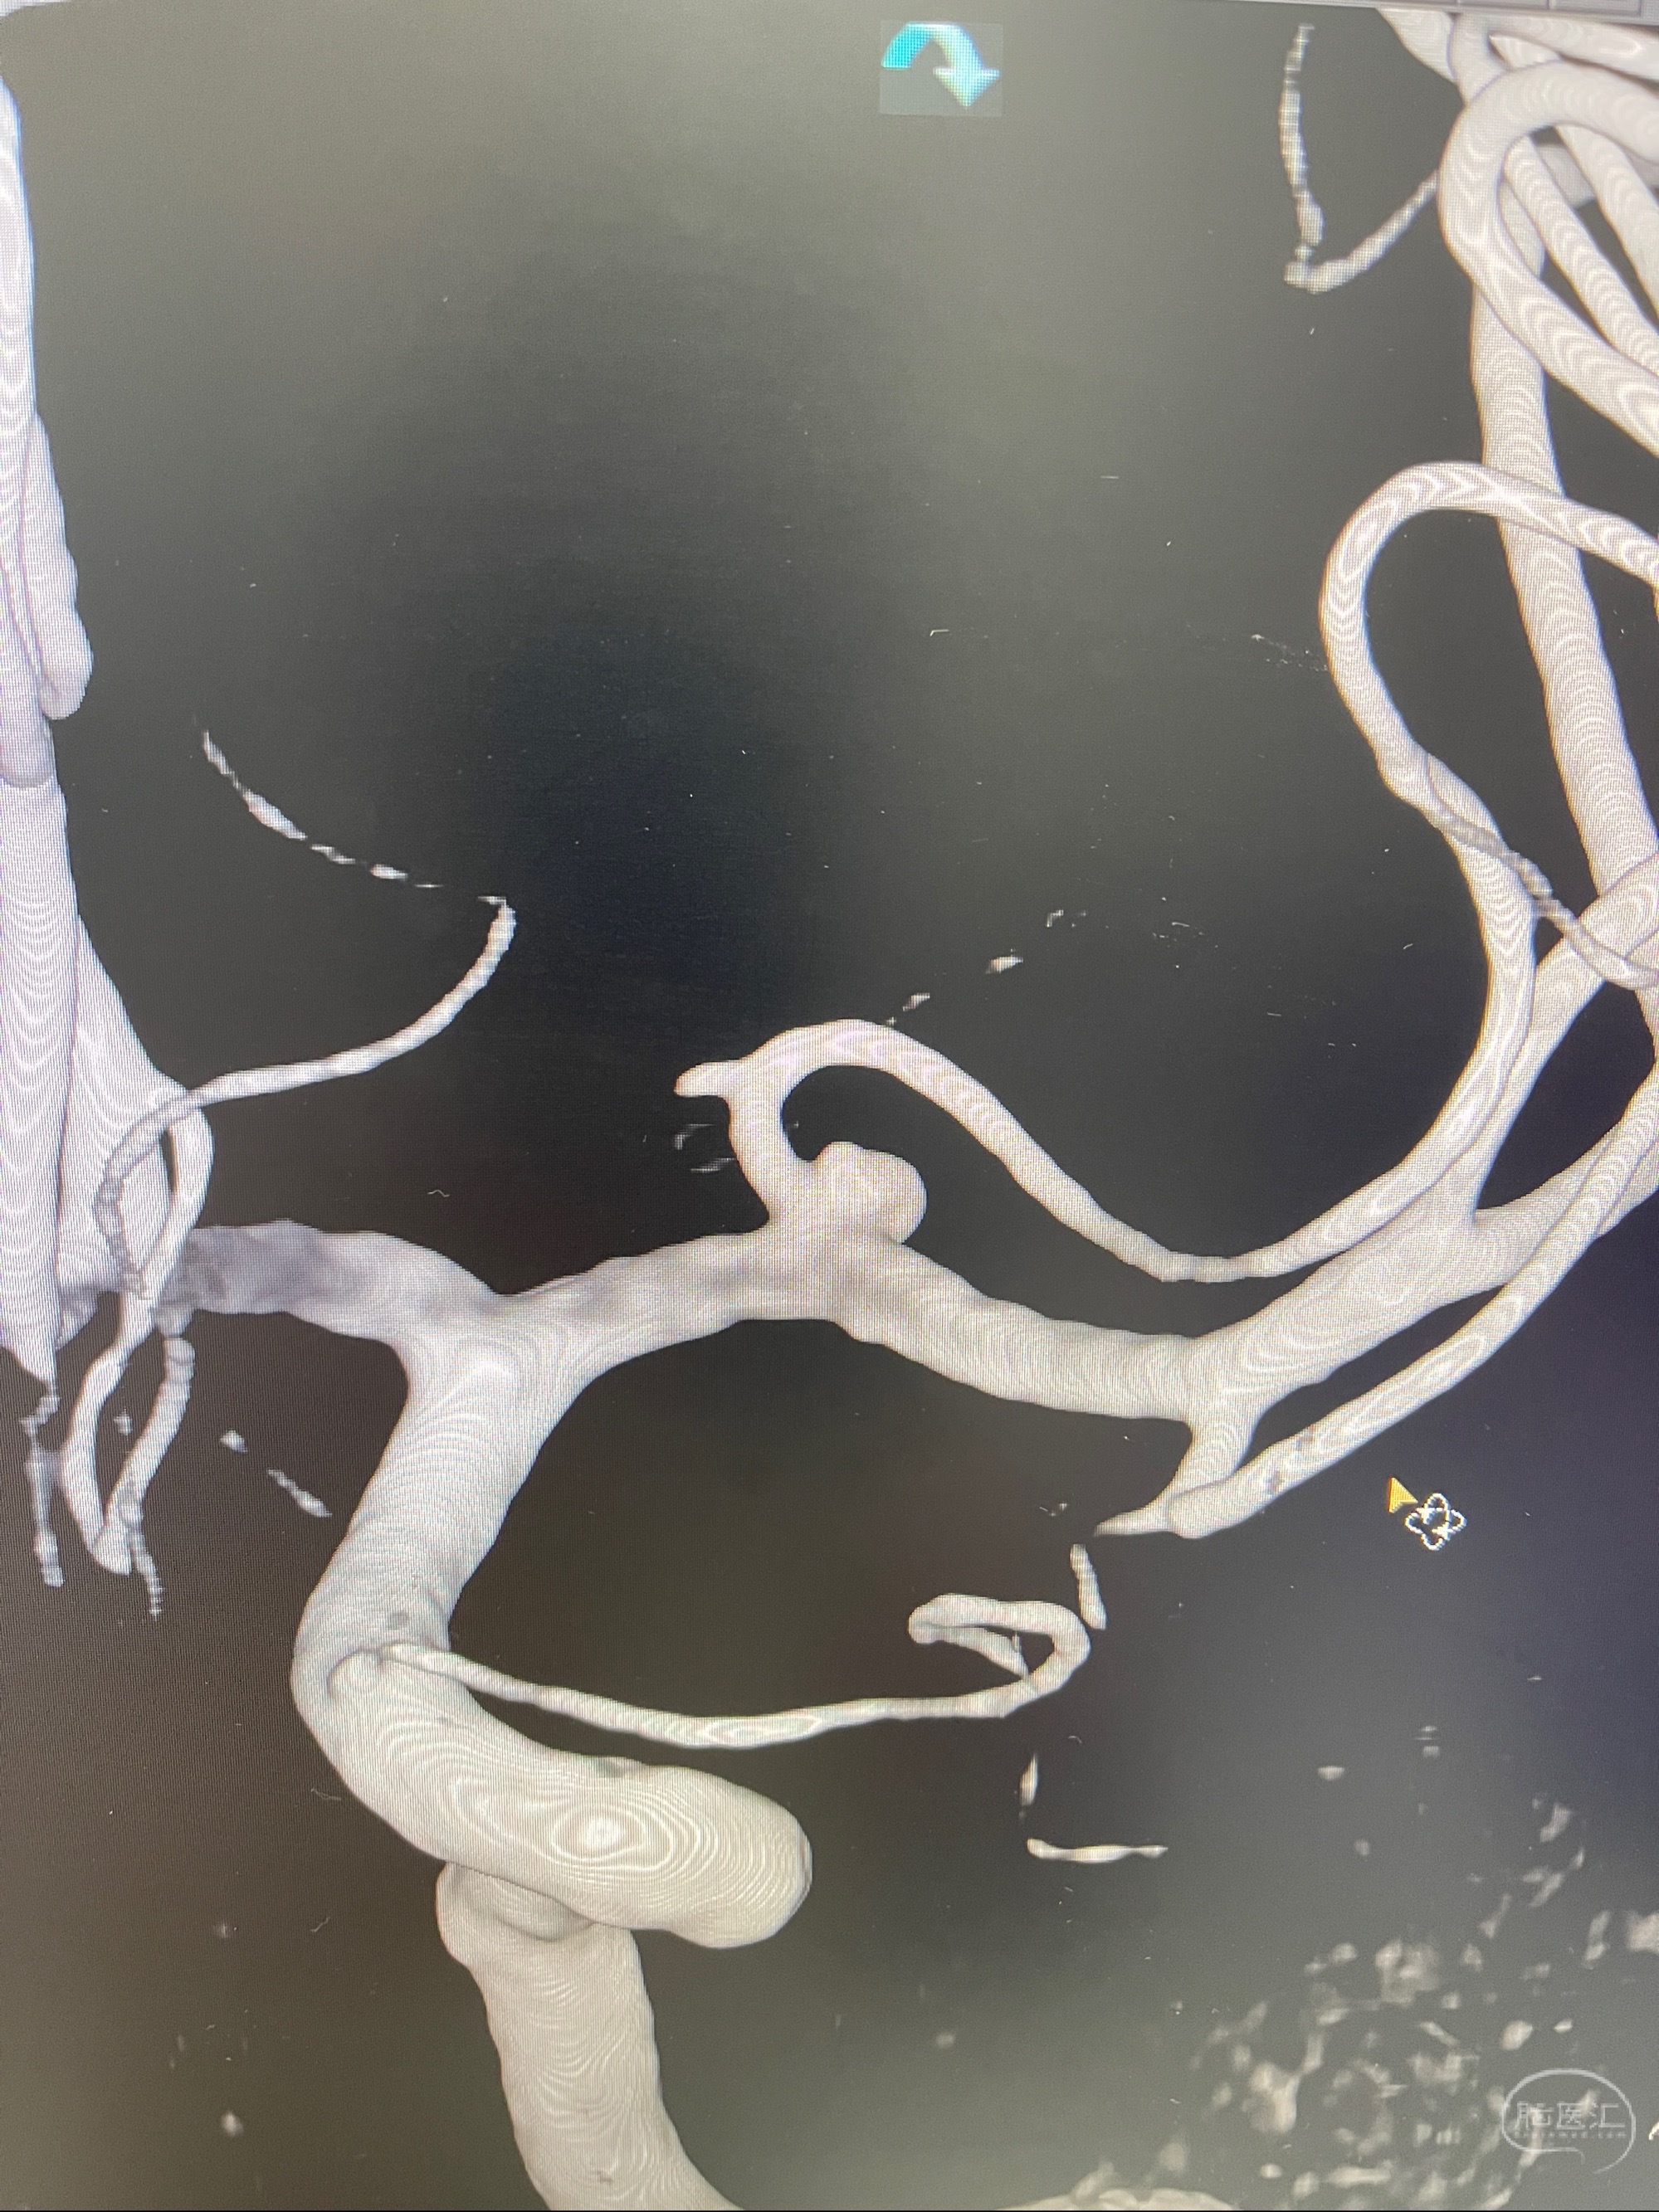

左侧大脑中动脉动脉瘤,约2.6-2.8-3.4-2mm大小(瘤颈部、瘤体部、瘤高)

1.左侧大脑中动脉动脉瘤,约2.6-2.8-3.4-2mm大小(瘤颈部、瘤体部、瘤高)